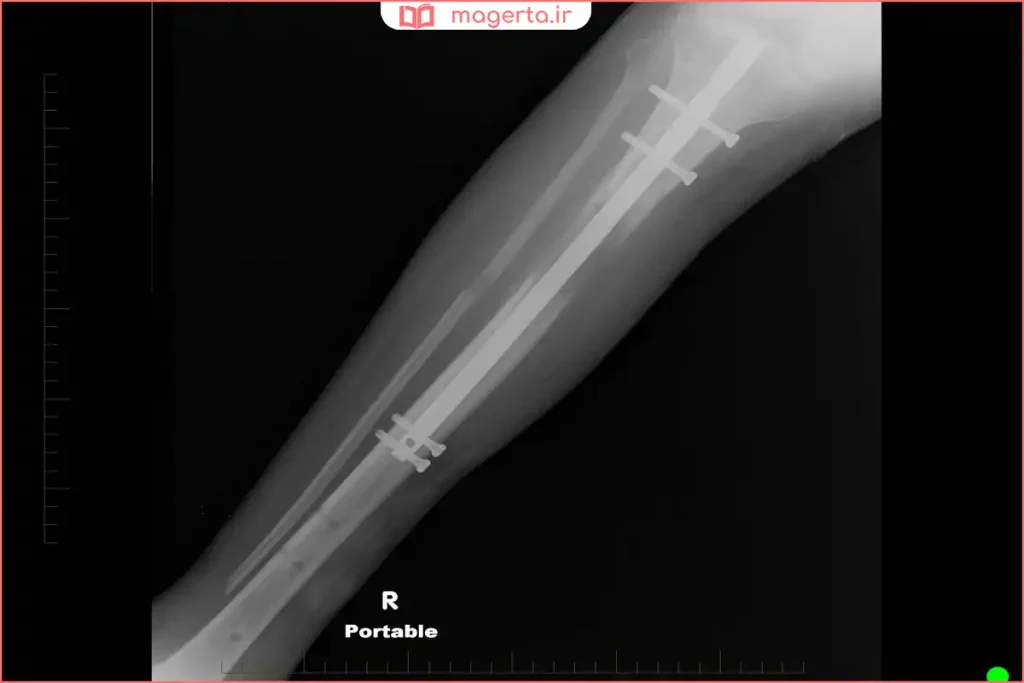

| ارتوپدی و تثبیت استخوان | پلاتین و صفحات برای شکستگیها | تثبیت شکستگی، تسریع بهبودی و کاهش درد |

پلاتین به دلیل زیستسازگاری فوقالعاده، مقاومت بینظیر در برابر خوردگی، پایداری شیمیایی و خواص الکتریکی مطلوب، در پزشکی جایگاه ویژهای دارد. از تثبیت استخوانهای شکسته و ساخت ایمپلنتهای دائمی گرفته تا تولید داروهای نجاتبخش ضدسرطان و الکترودهای دستگاههای پیشرفته مانند تحریک عمقی مغز، همگی نشاندهنده اهمیت این فلز گرانبها در بهبود کیفیت زندگی و افزایش طول عمر انسان هستند.